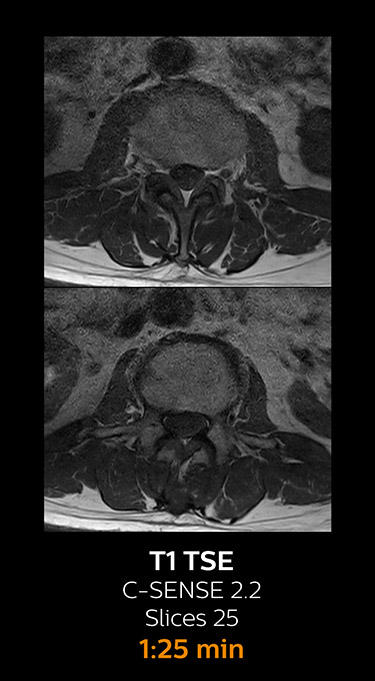

With Compressed SENSE, the scan time for the routine lumbar spine examination at KNC was reduced from 11:41 to 8:17 minutes,

MRI examination of the lumbar spine with Compressed SENSE

Ingenia 3.0T CX

Scan time 8:17 min. (was 11:41 min. without Compressed SENSE)